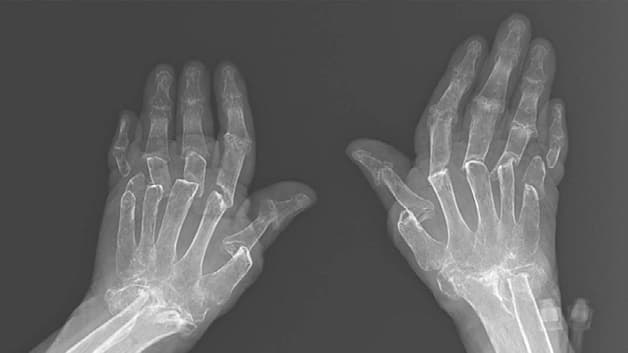

Hình ảnh chụp X-Quang của bệnh nhân bị viêm khớp dạng thấp.

Viêm khớp dạng thấp hay còn gọi là thấp khớp, viêm đa khớp dạng thấp. Đây là bệnh lý mạn tính do rối loạn tự miễn trong cơ thể gây ra. Bệnh xảy ra khi hệ thống miễn dịch tấn công nhầm vào các mô trong cơ thể, tạo ra phản ứng viêm khiến khớp bị sưng đau, xơ cứng. Viêm khớp dạng thấp có thể dẫn tới hủy xương, biến dạng khớp, ảnh hướng tới sinh hoạt hàng ngày của người bệnh.

Nguyên nhân sinh ra bệnh viêm khớp dạng thấp có thể được lý giải bằng cơ chế rối loạn miễn dịch. Cụ thể, hệ thống miễn dịch trong cơ thể tấn công lớp màng bao quanh khớp, dẫn đến viêm nhiễm. Màng hoạt dịch cũng được kéo dày lên, sưng phồng và chèn ép lên sụn và xương. Bên cạnh đó, gân và dây chằng có thể bị giãn, suy yếu dần làm biến dạng khớp.